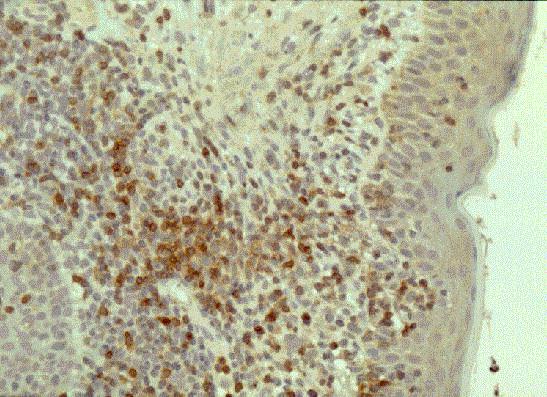

Con respecto al bcl-2, actualmente existen disponibles anticuerpos

monoclonales que funcionan perfectamente en parafina, sobre todo si se utiliza algún

sistema de desenmascaramiento antigénico por calor (microondas u olla a presión). La

tinción positiva ocurre a nivel citoplásmico, observándose por regla general una

expresión fuerte en el interior de los folículos neoplásicos y sólo algunas células

positivas en los folículos reactivos, correspondientes a linfocitos T (ver

Veloso et al, 1995). No obstante, es preciso considerar que existe un número de

linfomas foliculares negativo para bcl-2, tanto mayor cuanto más células grandes

componen el tumor. Además es preciso no interpretar erróneamente folículos primarios

con tinción positiva como tumorales (Piris MA, 1995).